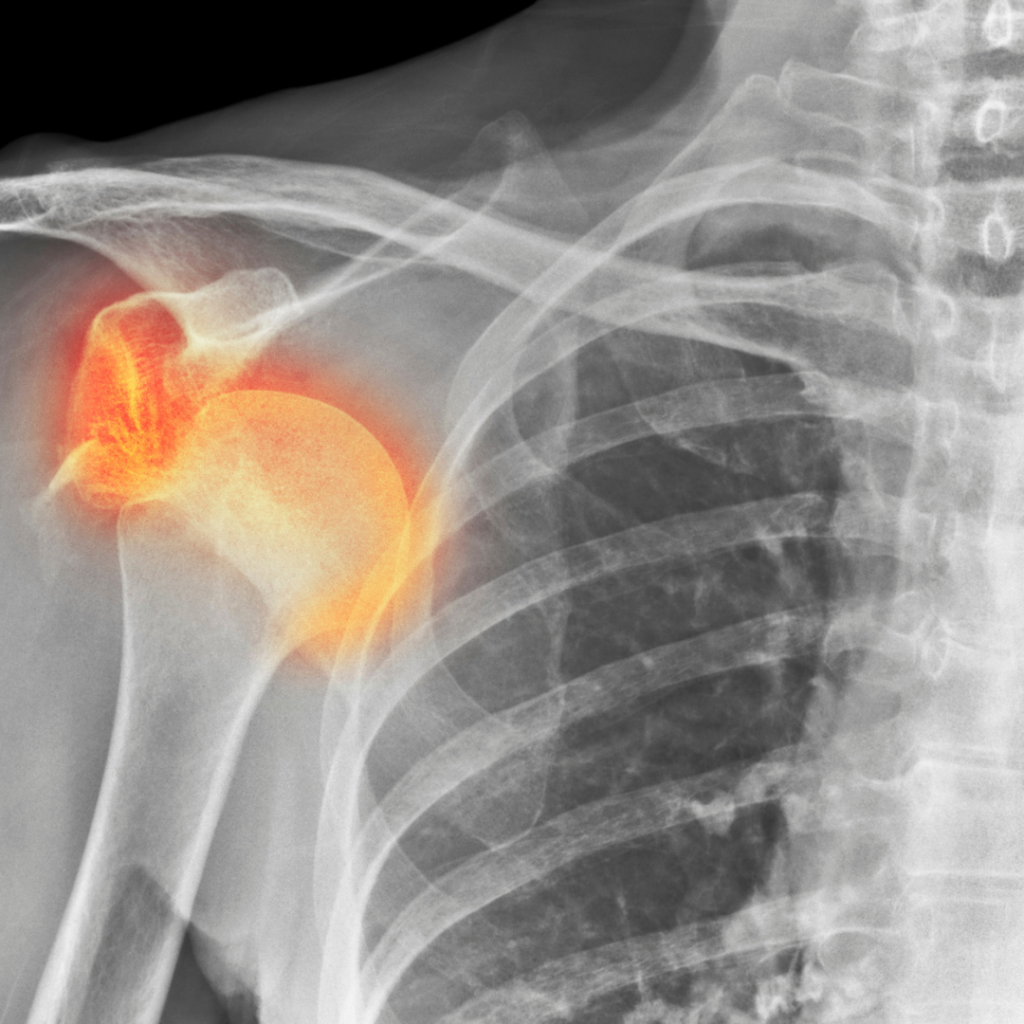

Do izpaha rame pride, ko glavica nadlahtnice izstopi iz sklepne ponvice, ki se nahaja na lopatici. Ob poškodbi je običajno prisotna bolečina. Pogosto se težave lahko zdravi konzervativno s pomočjo fizioterapije in kineziologije, ob ponavljajočih izpahih pa je včasih potrebno tudi operativno zdravljenje. V zapisu vam bomo predstavili nekatere ključne informacije ter kako poteka rehabilitacija po izpahu rame.

Izpah ramenskega obroča je pogosto posledica travmatičnih dogodkov, kot so padec, športna poškodba ali prometna nesreča. Sila, ki deluje na ramo, lahko povzroči, da glava nadlahtnice skoči iz sklepne ponvice lopatice. Izpah rame delimo na:

Simptomi: Običajni simptomi izpaha rame so močna bolečina, oteklina, rdečica ali modrica in omejen obseg gibljivosti. V nekaterih primerih lahko opazite vidno deformacijo ali vdolbino v rami, kamor se je nadlahtnica premaknila.